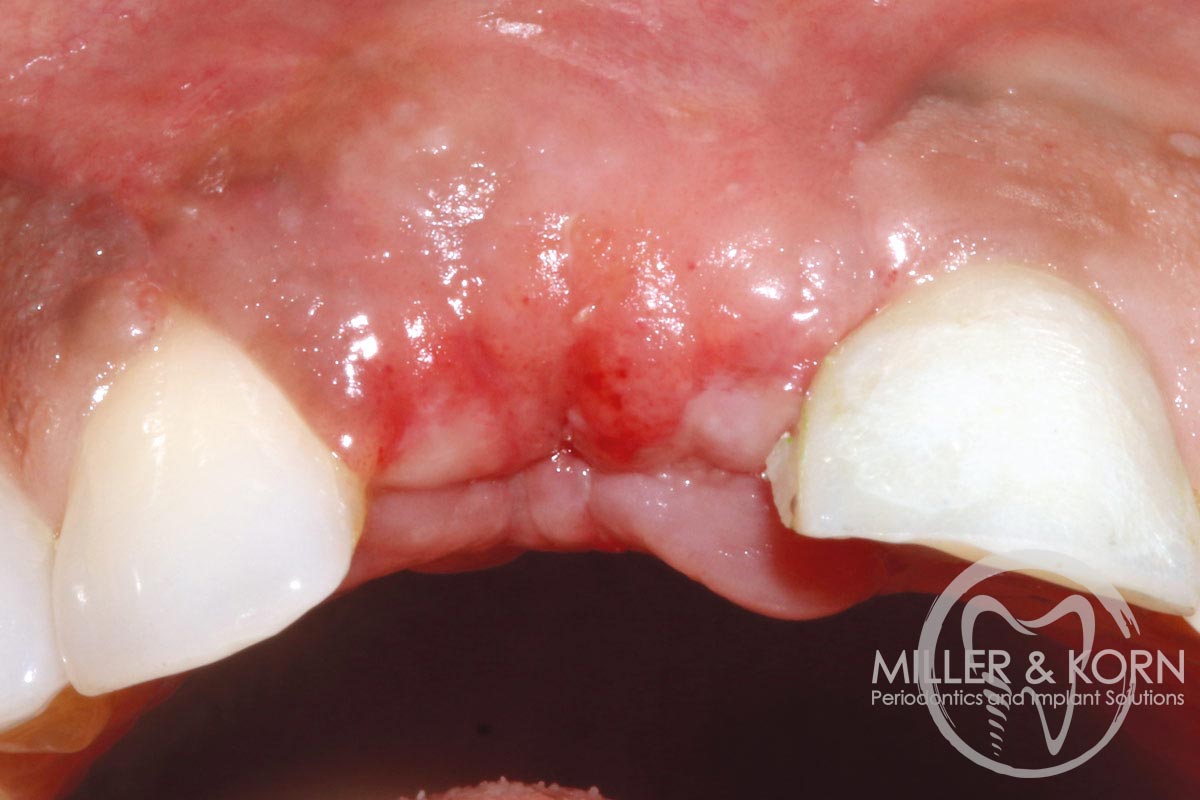

3/22 - Atraumatic extraction of tooth #11Immediate implant placement and regeneration of ridge using an allograft bone ring and Jason® membrane - Drs. Miller and Korn

4/22 - Full thickness flap elevation with vertical releasing incisions. Note, significant apical and buccal bone resorption after raising the flapImmediate implant placement and regeneration of ridge using an allograft bone ring and Jason® membrane - Drs. Miller and Korn